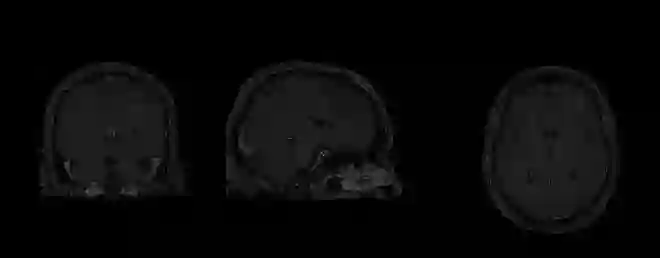

Magnetic Resonance Imaging (MRI) is the most commonly used non-intrusive technique for medical image acquisition. Brain tumor segmentation is the process of algorithmically identifying tumors in brain MRI scans. While many approaches have been proposed in the literature for brain tumor segmentation, this paper proposes a lightweight implementation of U-Net. Apart from providing real-time segmentation of MRI scans, the proposed architecture does not need large amount of data to train the proposed lightweight U-Net. Moreover, no additional data augmentation step is required. The lightweight U-Net shows very promising results on BITE dataset and it achieves a mean intersection-over-union (IoU) of 89% while outperforming the standard benchmark algorithms. Additionally, this work demonstrates an effective use of the three perspective planes, instead of the original three-dimensional volumetric images, for simplified brain tumor segmentation.